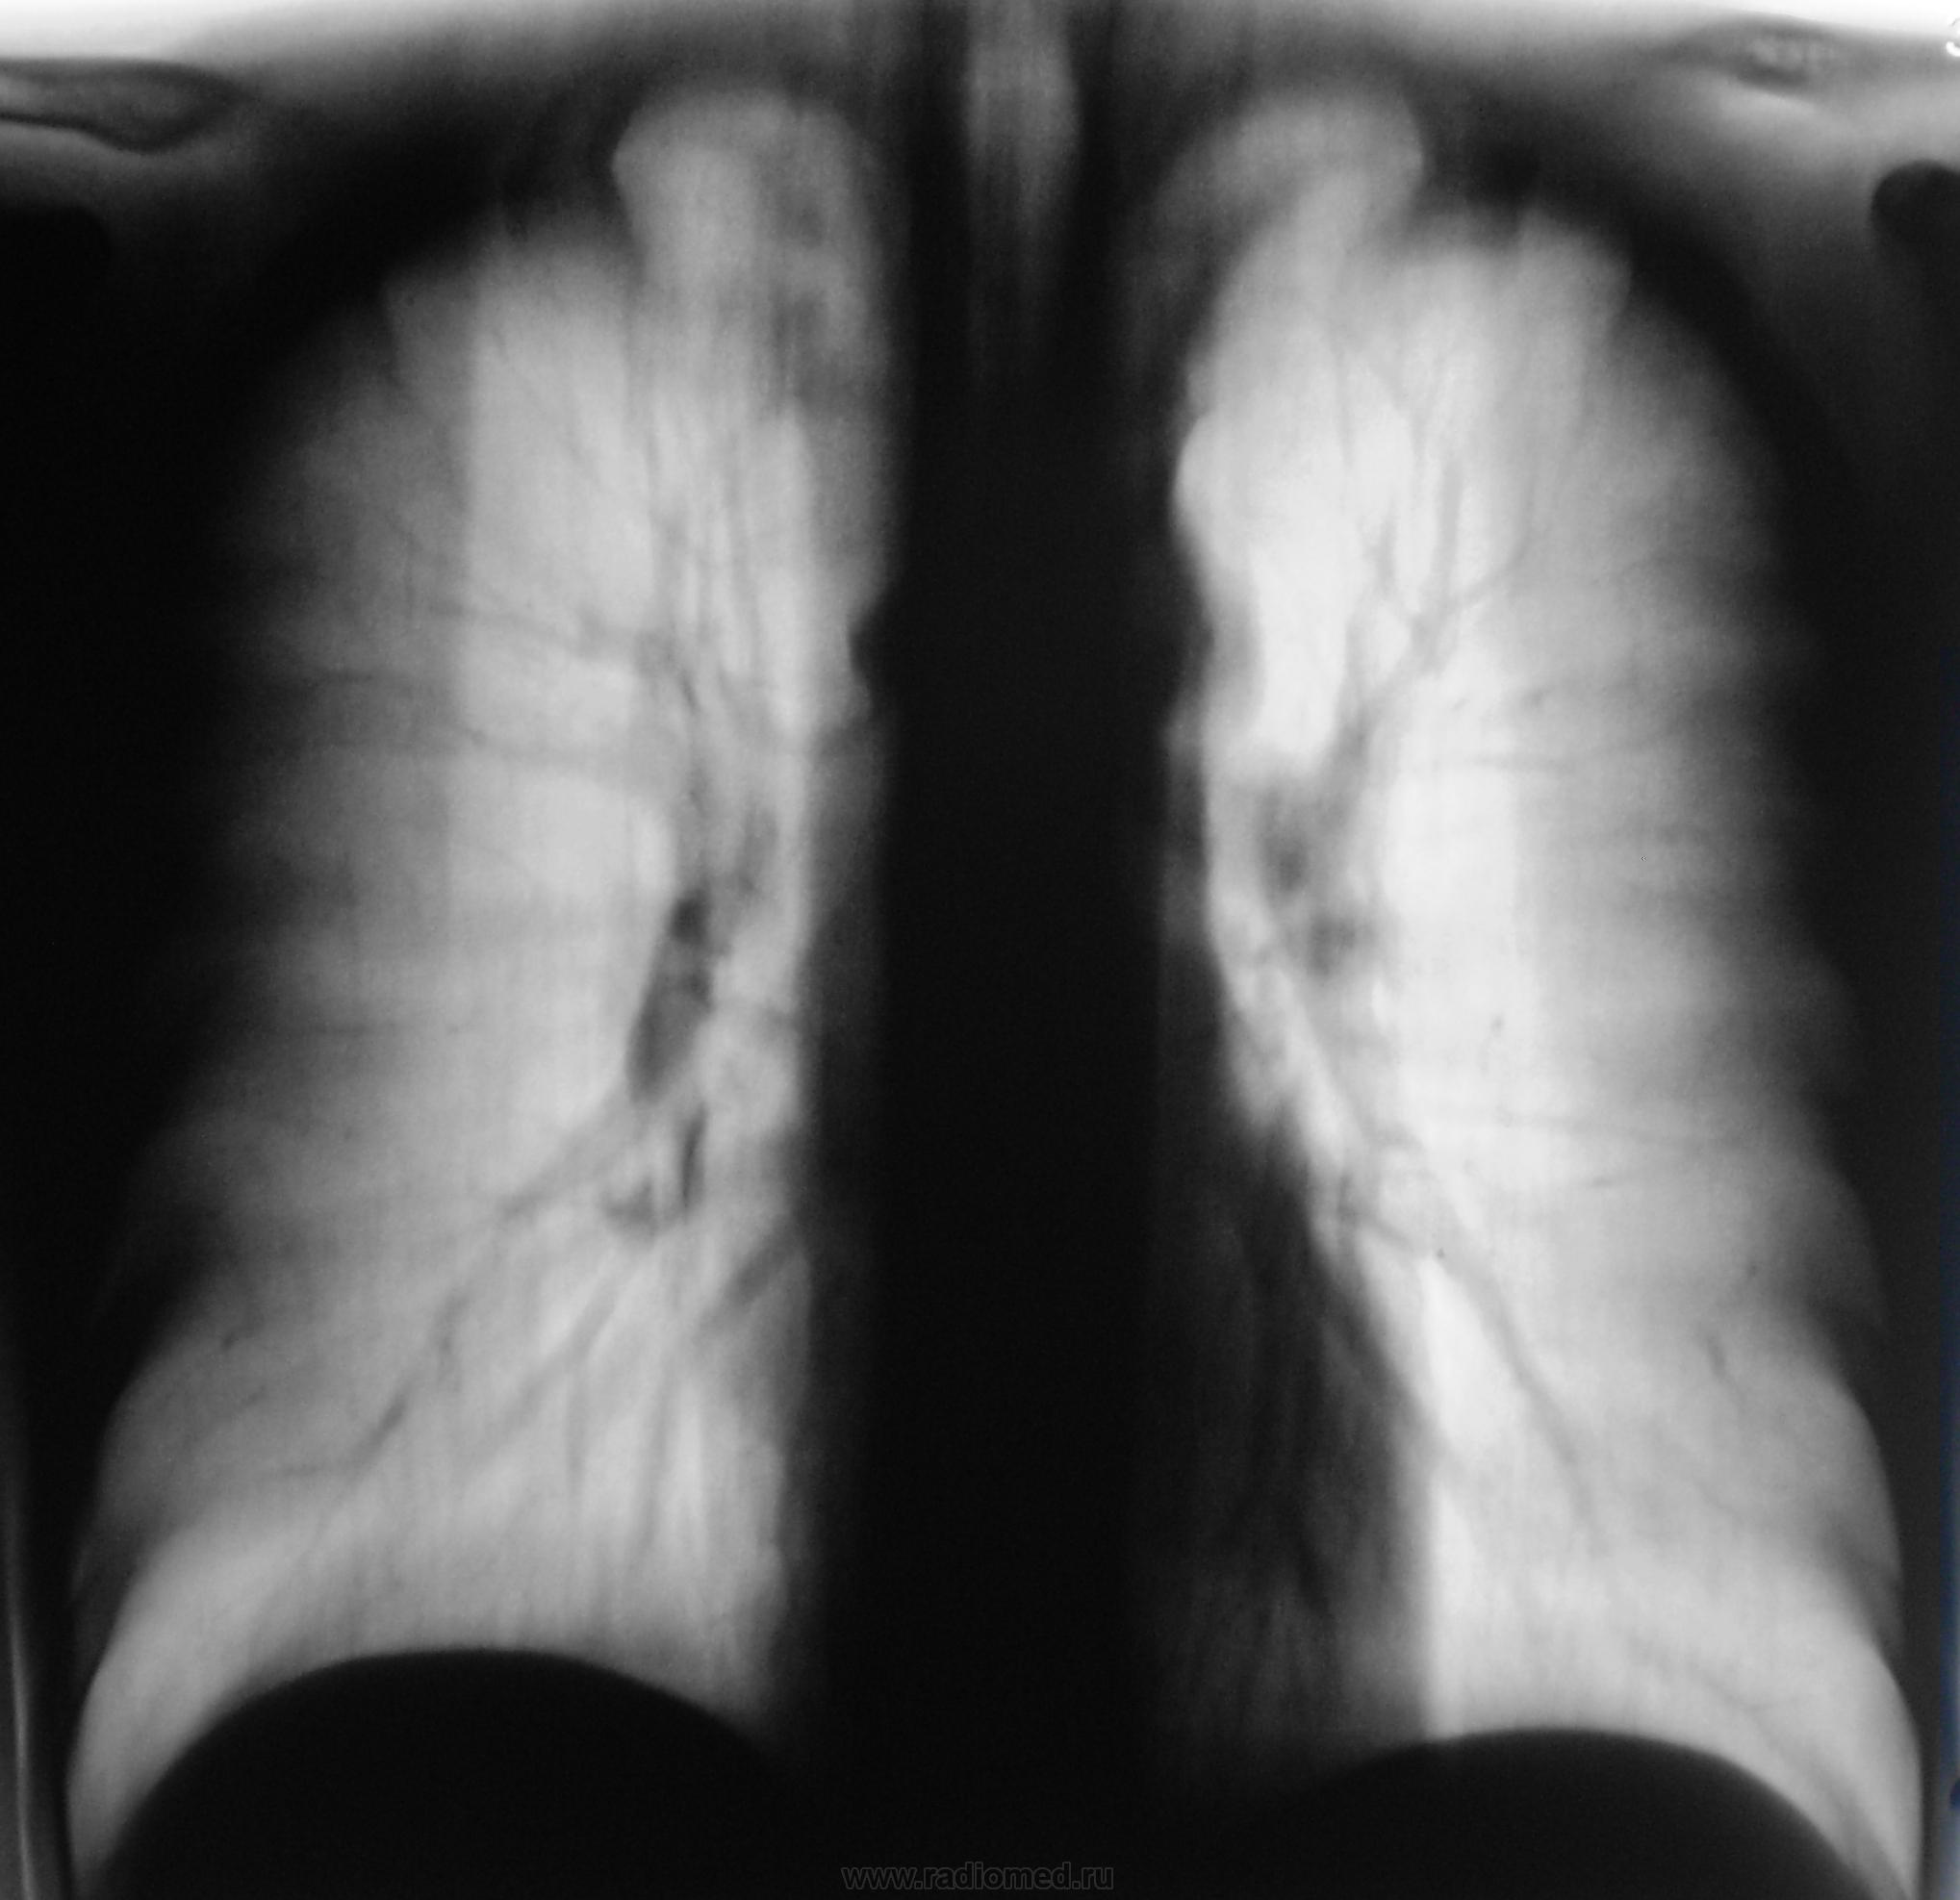

Но самое интересное то, что выставленные иллюстрации - это "вторая часть" (менее интересная), так называемого "Марлизонского балета". Первую часть сейчас выставлю.

Дело в том, что этого пациента я зацепил еще год тому назад.

Снимки ниже.

Снимки.